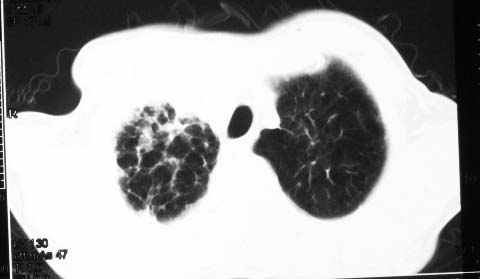

影象表现:右肺上叶大片状、网格状及索条致密影,蜂窝影,其内参杂斑点状小结节,密度不均匀,内见含气支气管像,纵隔内见肿大淋巴结.

影象表现:右肺上叶大片状、网格状及索条致密影,蜂窝影,其内参杂斑点状小结节,密度不均匀,内见枯枝样含气支气管像,纵隔内见肿大淋巴结.胸膜广泛增厚,前胸壁似受累.少量胸腔积液.纵隔内淋巴结的直径>1.5cm.右侧胸廓体积缩小.考虑:1 肺结核合并间质纤维化 2 细支气管肺泡癌

右肺上叶大片状、网格状及索条致密影,蜂窝影,其内参杂斑点状小结节,密度不均匀,内见枯枝样含气支气管像,纵隔内见肿大淋巴结.胸膜广泛增厚,前胸壁受累增厚.少量胸腔积液.纵隔内淋巴结的直径>1.5cm.右侧胸廓体积缩小.考虑: 细支气管肺泡癌并肺内癌性淋巴管炎。